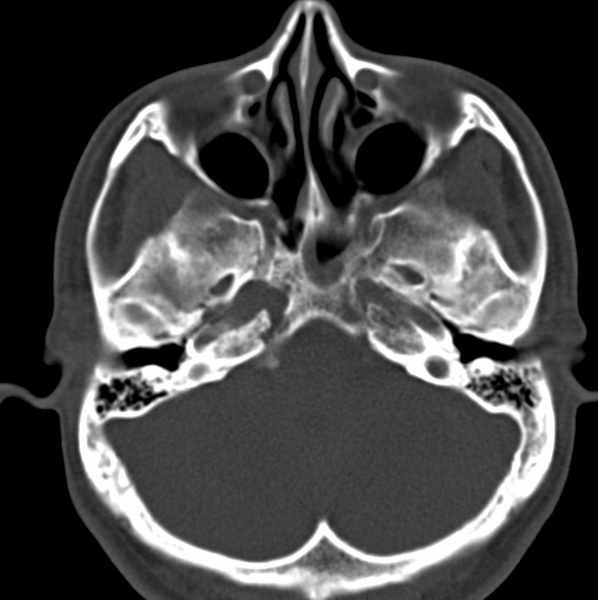

男、31、鼻咽部肿瘤放疗后请帮忙看看。

效果好,右侧破裂孔扩大,局部骨质缺损,为颅底骨质破坏。

1)鼻咽部肿瘤侵犯颅底放疗术后改变。2)左侧蝶窦炎。

咽后壁增厚,左侧咽鼓管隆突增大、咽鼓管咽口变浅,同侧咽旁间隙较窄。右侧颅底骨质破坏?为什么不在同一侧?

鼻咽部肿瘤侵犯颅底放疗术后改变.